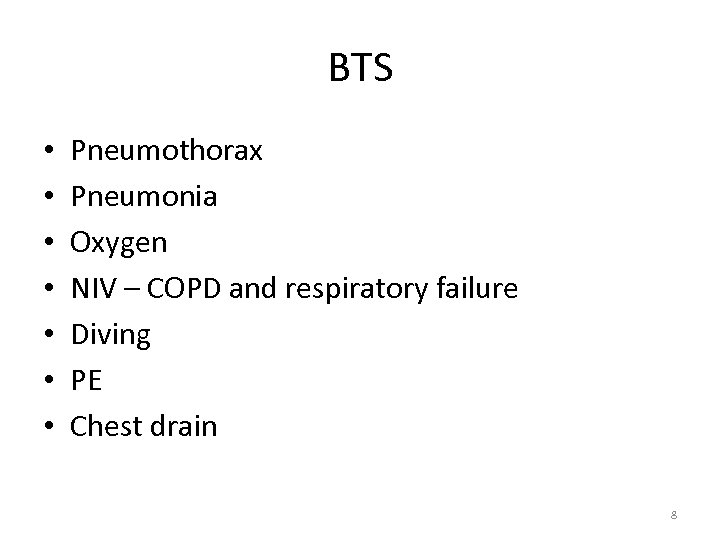

BTS • • Pneumothorax Pneumonia Oxygen NIV – COPD and respiratory failure Diving PE Chest drain 8